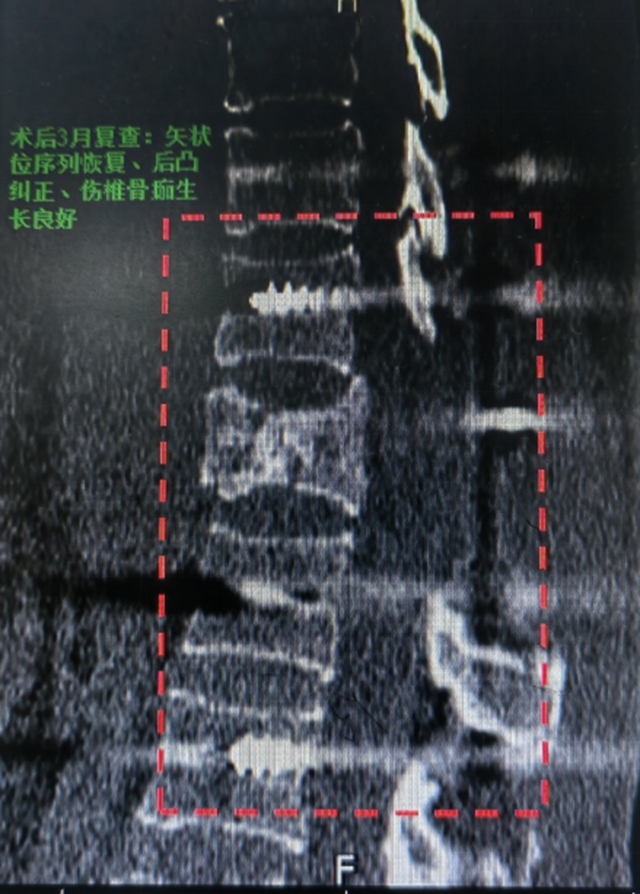

当日夜间,骨伤科脊柱·肿瘤二组罗成副主任医师、陈波主治医师顺利地给王女士实施了手术,术后王女士在科室接受系统中西医结合治疗后顺利出院。

术后3个月,王女士返院复查时的情况令人振奋:

双下肢可自主抬离床面,肌力恢复至3级(可抗重力运动);

在辅助下可独立站立并短时支撑;

感觉功能部分恢复,康复信心大幅增强。